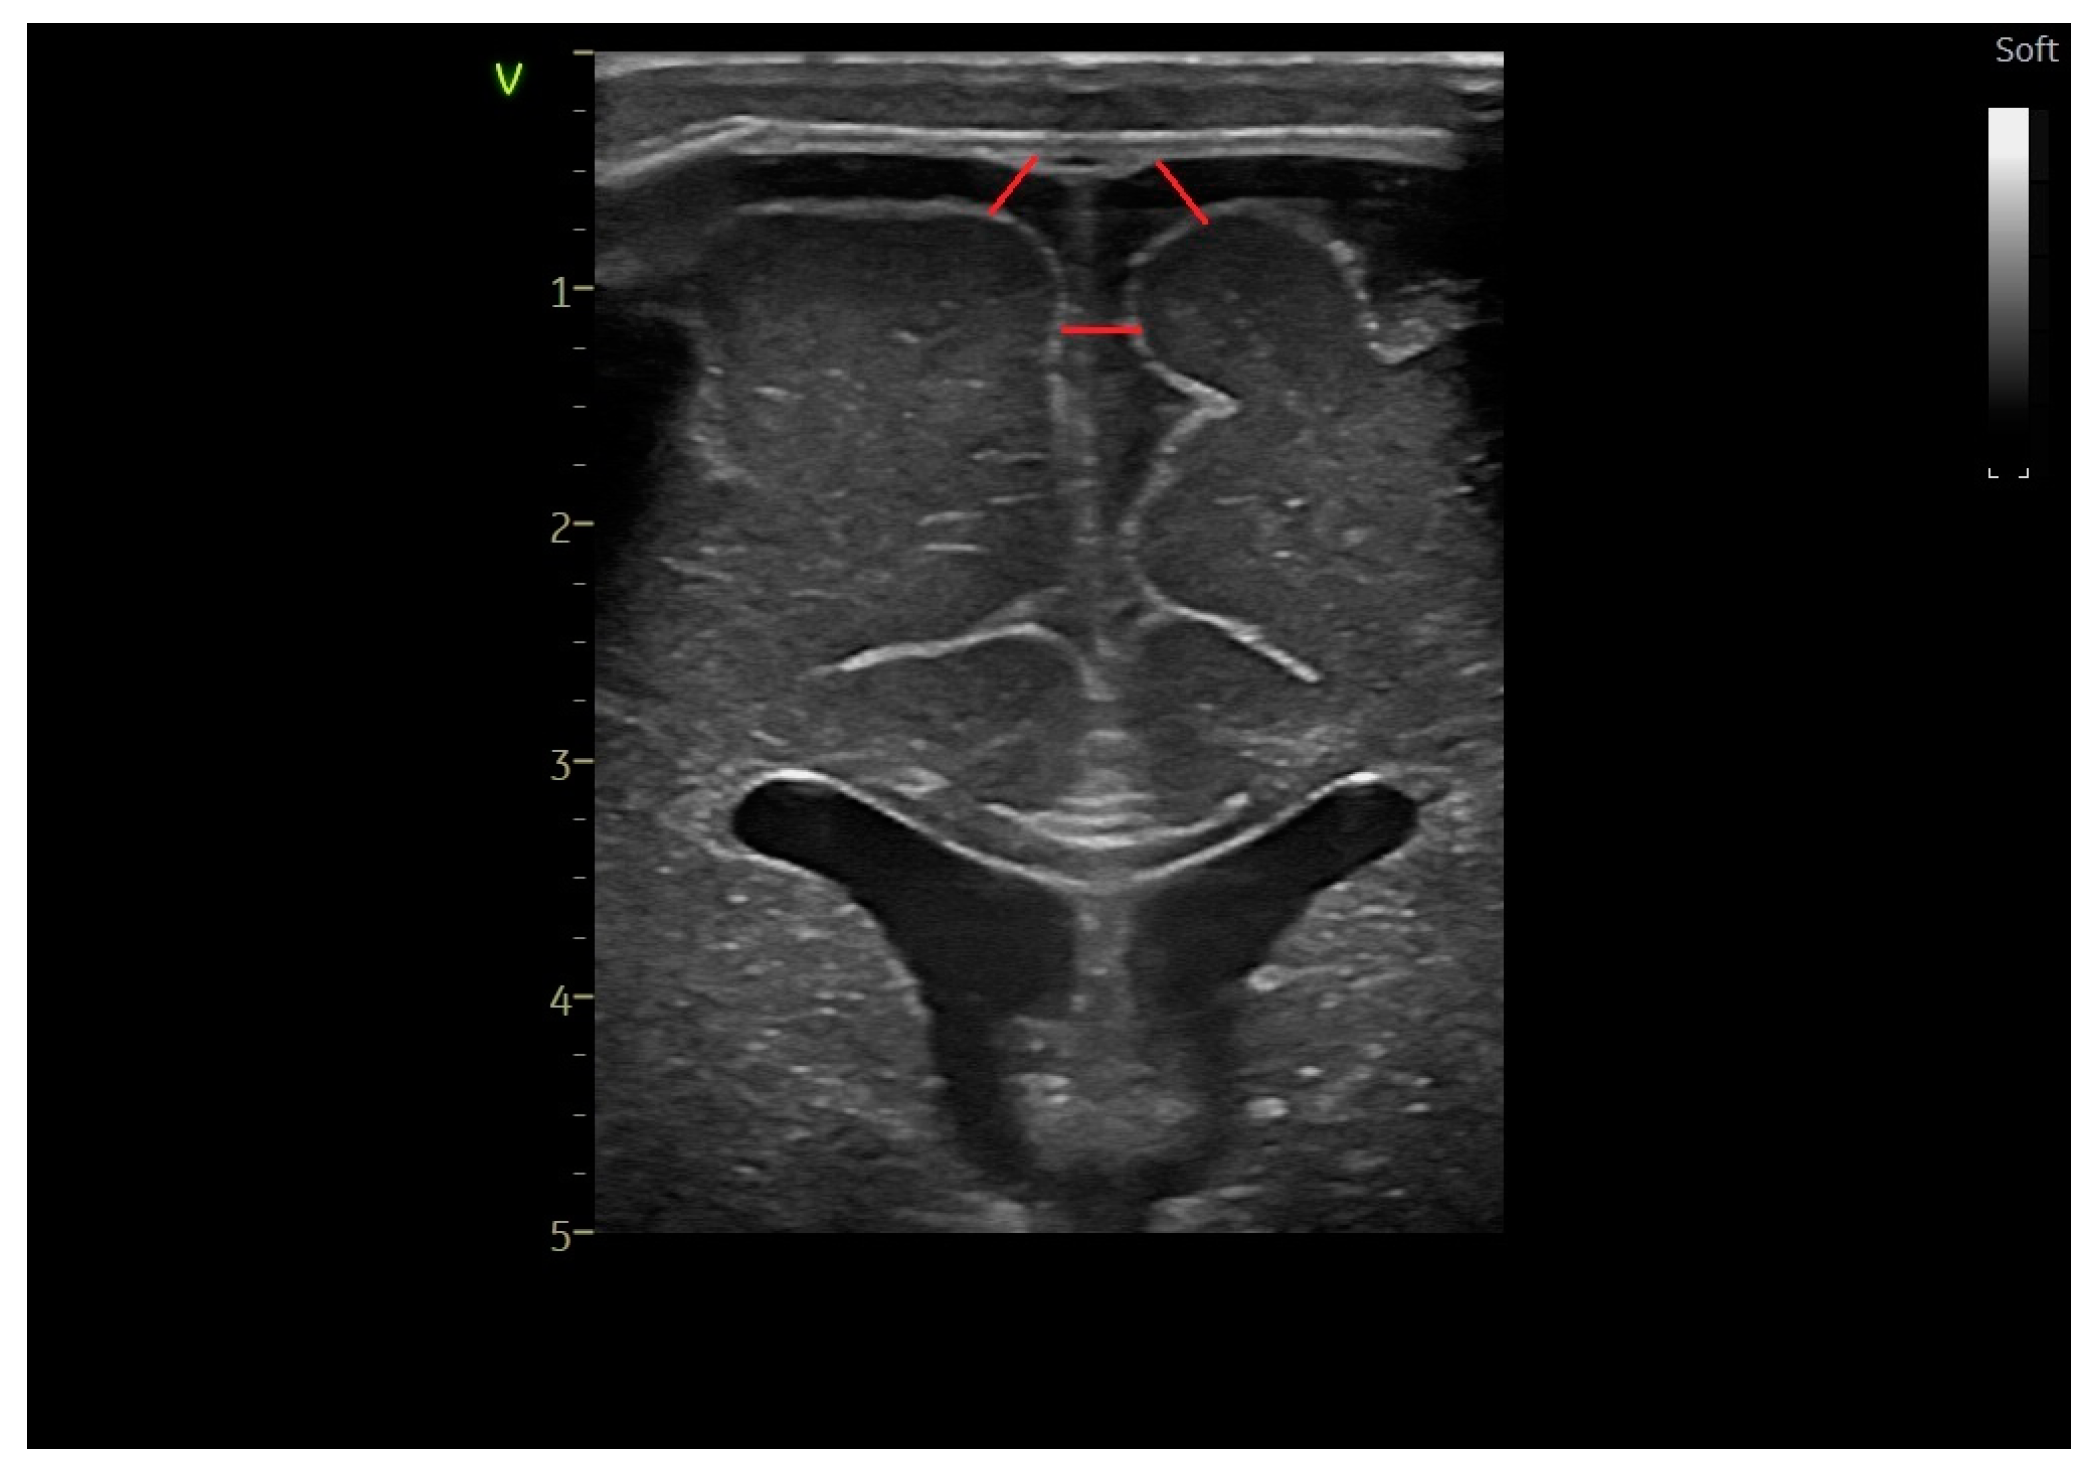

2.2. Head Ultrasound Measurements at TEA